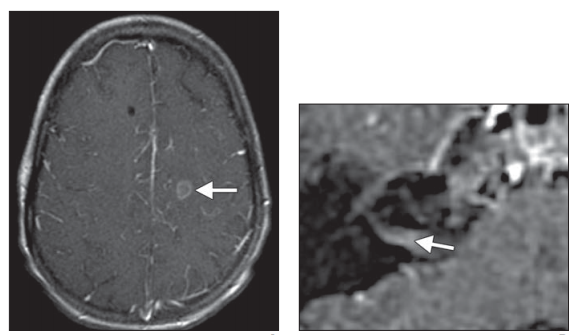

图8,T1增强,Bell麻痹患者,左侧面神经颅内段、迷路段、膝状神经节、鼓室段、迷路段较对侧均明显增强

图9,T1增强,中枢神经系统淋巴瘤,右侧面神经颅内段异常强化(终于不是迷路段和膝状神经节了)